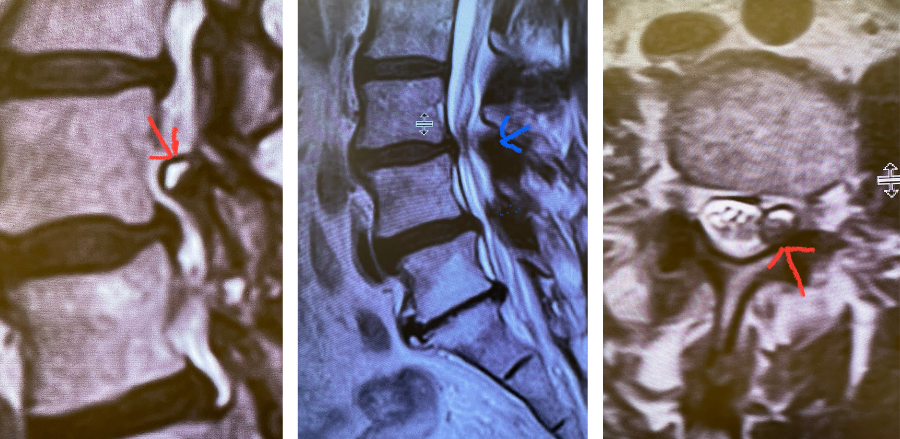

This 63-year-old female presents with nine months of low back pain and pain radiating to the lower extremities with the left leg worse than the right. The patient complained of numbness and tingling as well. The pain was exacerbated by standing, walking, and coughing. An MRI demonstrated severe lumbar stenosis L3-L5 with a superimposed left L3-4 synovial cyst (Fig 1).

Fig 1: Sagittal and axial T2-weighted MRI images demonstrating a large superiority-oriented synovial cyst (red arrow) at L4-5. The cyst is below the exiting L4 nerve root and hence compresses the descending L5 root. Note the additional thickened ligamentum flavum and slight spondylolistheses at L3-4 and L4-5 (blue arrow).

The patient also had a slight spondylolisthesis at L3-4 and L4-5. The patient failed all means of conservative management including medications, physical therapy, and epidural injections. The patient elected to proceed with a decompressive laminectomy and in-situ fusion. During the procedure we encountered a thick-walled cyst that melded with the dura. We first found the descending left L4 nerve root and separated the cyst and proceeded to in essence bite away the cyst with an instrument. We decompressed the L4 nerve root as it entered its foramina by removing the majority of the cyst wall. There was thick gray gelatinous material within the cyst. Part of the cyst wall seemed to be continuous with the dura and left it alone as it caused no pressure on the root. After our decompression we decided to perform an in-situ fusion as we had relative preservation of the joint complexes. Post operatively, she had an uneventful course with significant relief of her leg pain.